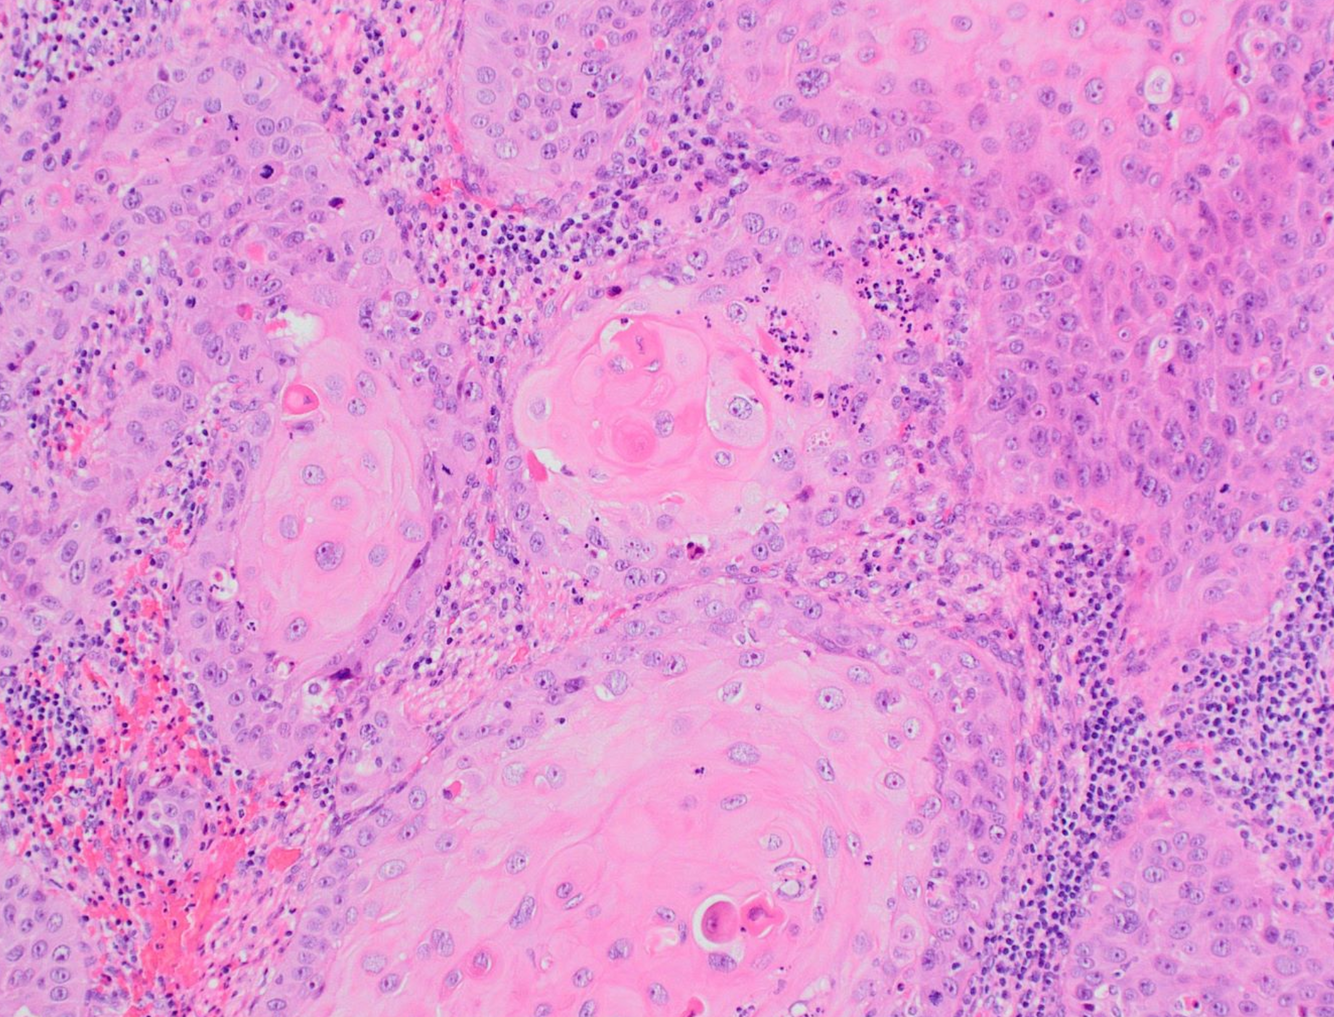

**Primary squamous cell carcinoma of the bladder

1.5-2.5% of bladder cancers in the US, but >50% of bladder cancers in schistosomiasis-endemic regions (~75% of cases in Egypt).

Histology: Squamoid features, sometimes with keratinization and often with intercellular bridging. Since schistosoma is associated, schistosoma eggs may be present and you should look for these if you are suspecting SCC of the bladder. Also reviewing travel history wouldn’t hurt.

Often presents with advanced stage, >95% muscle-invading by presentation. 20% LN involvement, but low rate of distal metastasis. 90% of associated deaths are due to local recurrence.

Do not respond well to chemo - early cystectomy is advised.